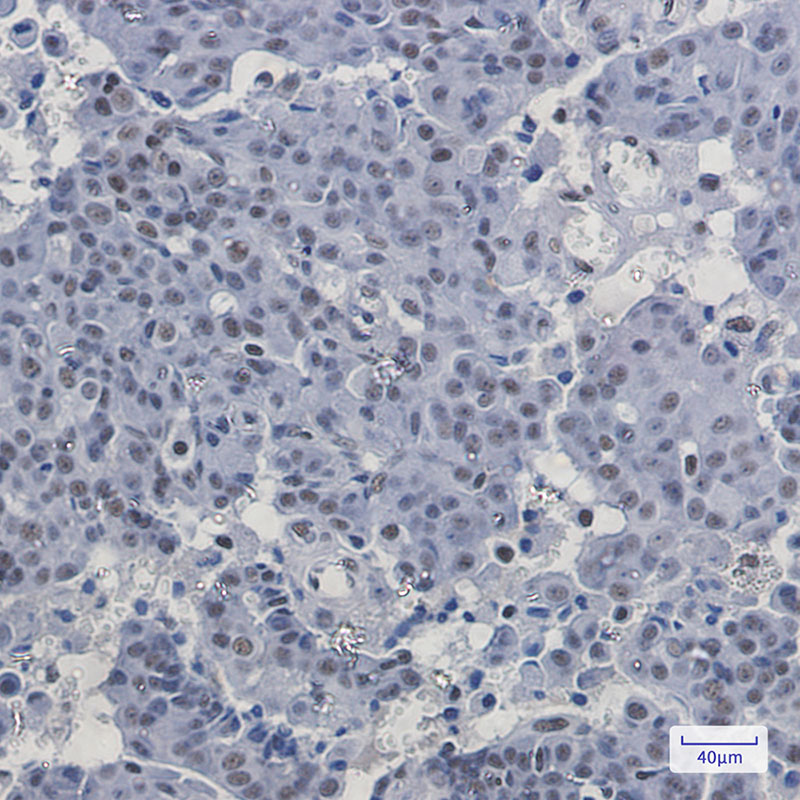

IHC 1/50-1/100 Human,Mouse,Rat

Antibodies targeting PABPN1 are essential tools for studying its role in RNA metabolism, cellular stress responses, and disease mechanisms. They are widely used in techniques like Western blotting, immunofluorescence, and immunohistochemistry to detect endogenous PABPN1 levels, localization, and pathological aggregates in OPMD models. Due to its conserved structure and ubiquitous expression, generating specific antibodies requires careful validation to avoid cross-reactivity with other RNA-binding proteins. Commercial antibodies often target epitopes within the N-terminal or RRM regions. Studies using PABPN1 antibodies have elucidated its interactions with RNA-processing complexes and its aggregation propensity in neurodegenerative contexts. These tools also aid in diagnosing OPMD and screening therapeutic strategies aimed at reducing toxic nuclear inclusions.